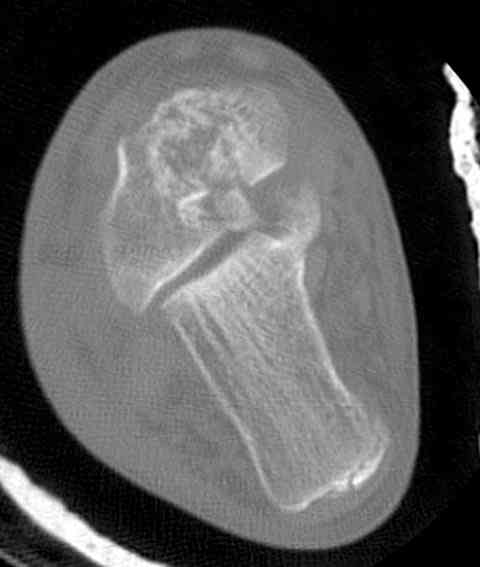

а основании двух видов ренгенограмм невозможно радикально решить о необходимости открытой репозиции или первичного артродеза.

Для оценки состояния нужны дополнительные исследования, например Canale или Broden ренгенограммы и Компьютерная томография.

При переломах тарана всегда имеется риск AVN, а классификация Hawkins поможет разобраться с предполагаемыми осложнениями.

Если в первом типе, когда перелом шейки без смещения, тогда AVN менее 10%, при втором типе когда имеется смещение и вывих тарана в субталарном сочленении меньше 40%, а при типе III когда смещение в голеностопном и субталарном суставах - около 90% и в типе IV, когда происходит полный вывих, риск AVN достигает 100%.

На ренгенограмме не уловил многоскольчатость тарана, чтобы доказать, конечно, можно было исследовать на КТ, потом КТ дает ориентацию фрагментов.

Два фрагмента суставной поверхности тарана можно восстановить боковой компрессией шурупами и дополнительно костная пластика.

(кстати, на нашем случае была применена костная пластика-allograft crouton для заполнения дефектов)